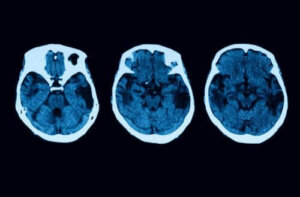

- Starten på demens: en person med detta tillstånd kommer uppvisa hypometabolism och hypoperfusion, vilka kan upptäckas tack vare ett test som involverar neuroavbildning. Notera dock att demens endast uppstår i sjukdomens senare skeden.

De diagnostiska testerna slutar dock inte där. För att undanröja alla tvivel kommer man utföra andra neurologiska tester, såsom magnetisk resonanstomografi och liknande. Om allt pekar på denna sjukdom finns det olika behandlingar.